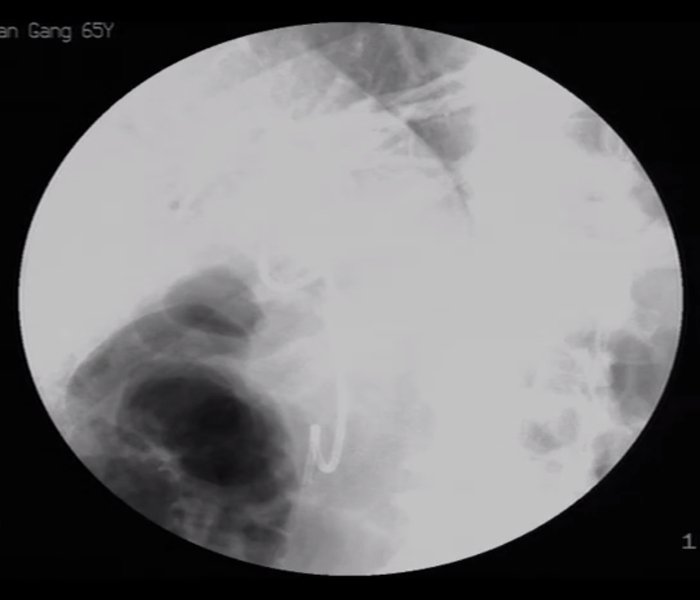

患者男,56岁,十二指肠镜提示慢性胰腺炎,CT下显示胰管结石。

CT下可见,结石狭窄处

导丝已插入胰管(右上